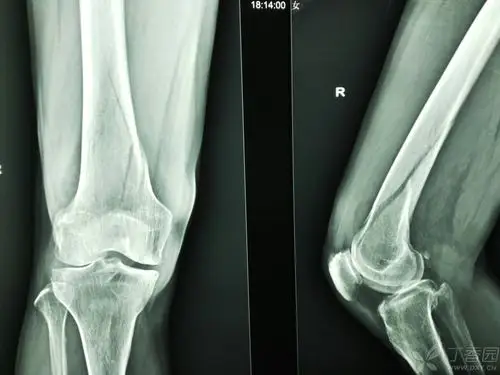

股骨髁骨折,主要并发症是什么?容易和哪些疾病混肴?预后如何?

一例股骨远端内髁骨折,求治疗方案!